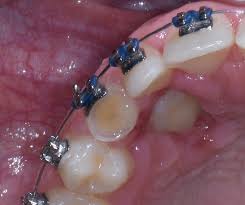

Natural autonomous eruption and forced eruption under orthodontic traction. Postoperative pain experienced by patients was similar, but regression of pain was faster in closed eruption technique. Forced eruption can preserve the natural root system and related periodontal architecture, resulting in years of additional service for the patient. It also can maintain adjacent tooth structure while retaining the option for future implant reconstruction. The postoperative recovery was longer after open eruption than close eruption technique (p = 0.000). 26,27 in the case shown here, closed eruption was chosen for the impacted central and. Dr vanarsdall recommends open exposure with a repositioned gingival flap (pediculated connective tissue graft) above the impacted canine. Management of unerupted maxillary incisors 6 5.4 incisor removal 5.5 ankylosed maxillary incisors.

Patients perception of recovery after exposure of impacted teeth: The difference in time required for the two techniques was statically significant (p = 0.000). The closed technique and the open technique. This facilitates eruption and orthodontic traction. Closed eruption technique for surgical exposure 3 surgical approach can be used 1. The postoperative recovery was longer after open eruption than close eruption technique (p = 0.000). It also can maintain adjacent tooth structure while retaining the option for future implant reconstruction. (1) window technique, (2) full flap open procedure, and (3) apically repositioned flap technique.

Chaushu s(1), becker a, zeltser r, vasker n, chaushu g. Preorthodontic exposure and autonomous eruption The open exposure technique consists of surgical removal of the tissue covering the tooth, leaving it exposed to the oral cavity. Given the reported success of forced eruption, the technique requires… continue reading The present study provides information to patients and clinicians. Duration of surgical procedure (in min) click here to view Dr vanarsdall recommends open exposure with a repositioned gingival flap (pediculated connective tissue graft) above the impacted canine. Apically position flap the goal is to choose a technique that exposes the canine within the a zone of keratinized mucosa without involvement of the cementoenamel junction 27. The open eruption technique may be performed in two different ways, as described below. If the canine crown is positioned distal to the mesial aspect of the lateral incisor, an open technique is performed. Forced eruption can preserve the natural root system and related periodontal architecture, resulting in years of additional service for the patient. Open eruption through a window; In this technique sufficient space.